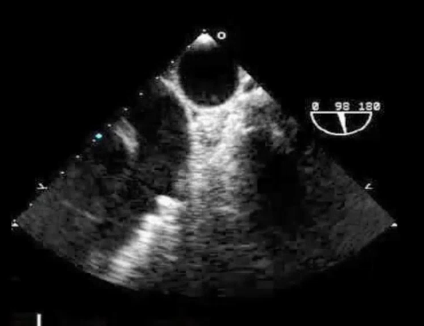

Mid Esophageal 5C

ME 5C 0 degree

Firt view that we get on TEE

Mid esophageal 5 chamber View

0 degree

Mid Esophageal 4C ME 4C 0 degree after 5 chamber we antegrade

32